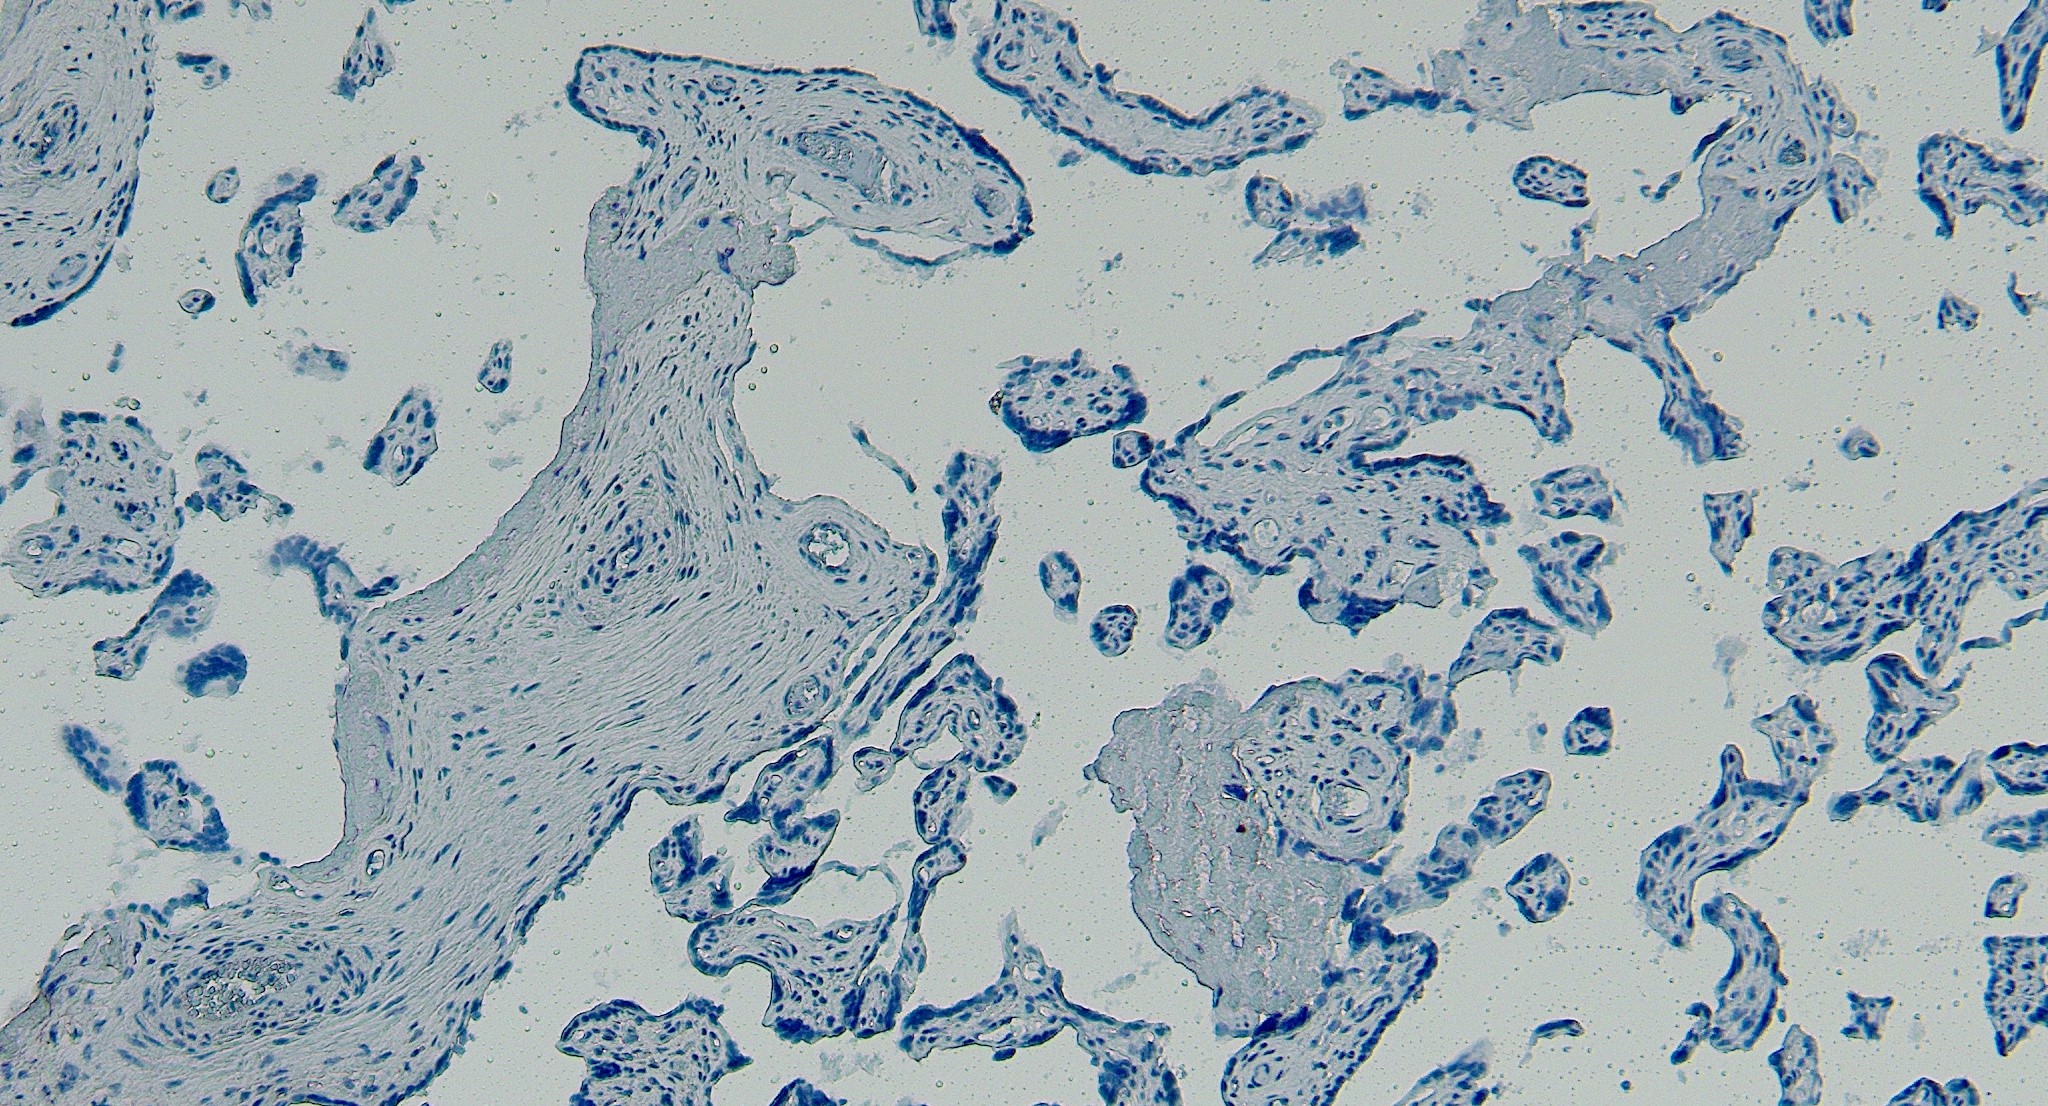

IHC Results Paraffin embedded Human Brain (Cortex) and Placenta. Recommended concentration: 5µg/ml. | |